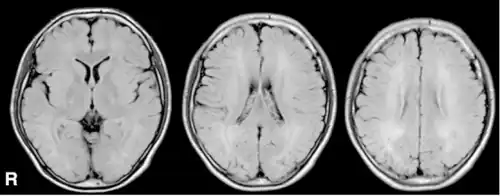

MRI, FLAIR -diffuse signal increase of deep white matter. | |